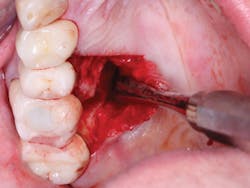

Figure 7: This shows severe postoperative pain caused by removal of large lingual periapical infection on first molar.

Figure 8: Closed wound of patient in Figure 7 healed rapidly with diminishing pain after 24 hours.